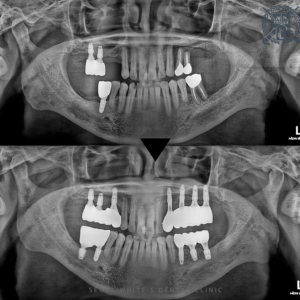

영도치과, 임플란트로 어금니 기능과 양측 균형을 맞춰요! 안녕하세요. 영도치과 서울화이트S치과 입니다. 치과내원이 늦으시는 이유 중에 “불편한 곳이 있지만 피해서 다른 쪽으로 식사해왔어요.”라고 말씀하시는 분이 많이 계십니다. 치아의 갯수가…